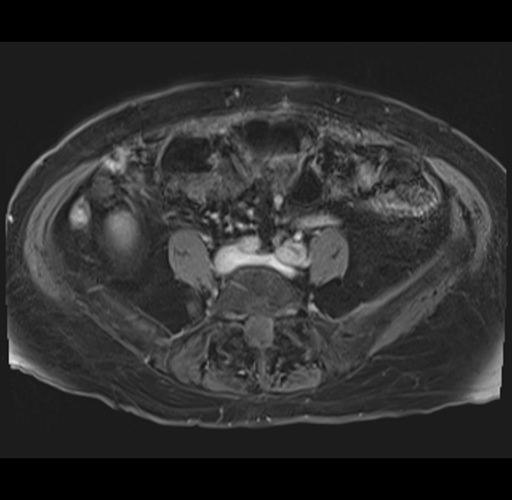

MRI T1